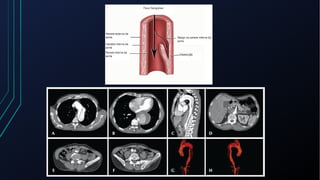

Dor torácica pode ter diversas causas, incluindo cardíacas como síndrome coronariana aguda, dissecção de aorta e pericardite, e não cardíacas como problemas pulmonares, musculoesqueléticos e do trato gastrointestinal. É importante avaliar a história clínica, características da dor e exame físico para identificar a possível causa e orientar o tratamento adequado.